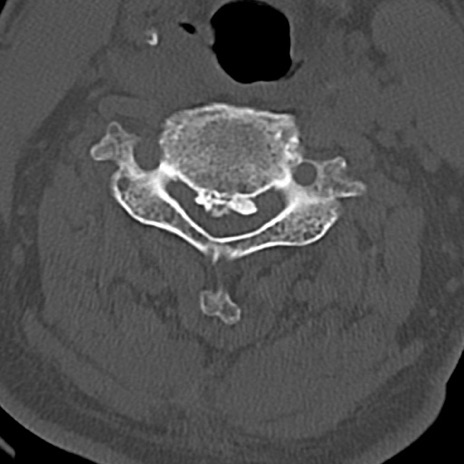

頚椎CT

横断像